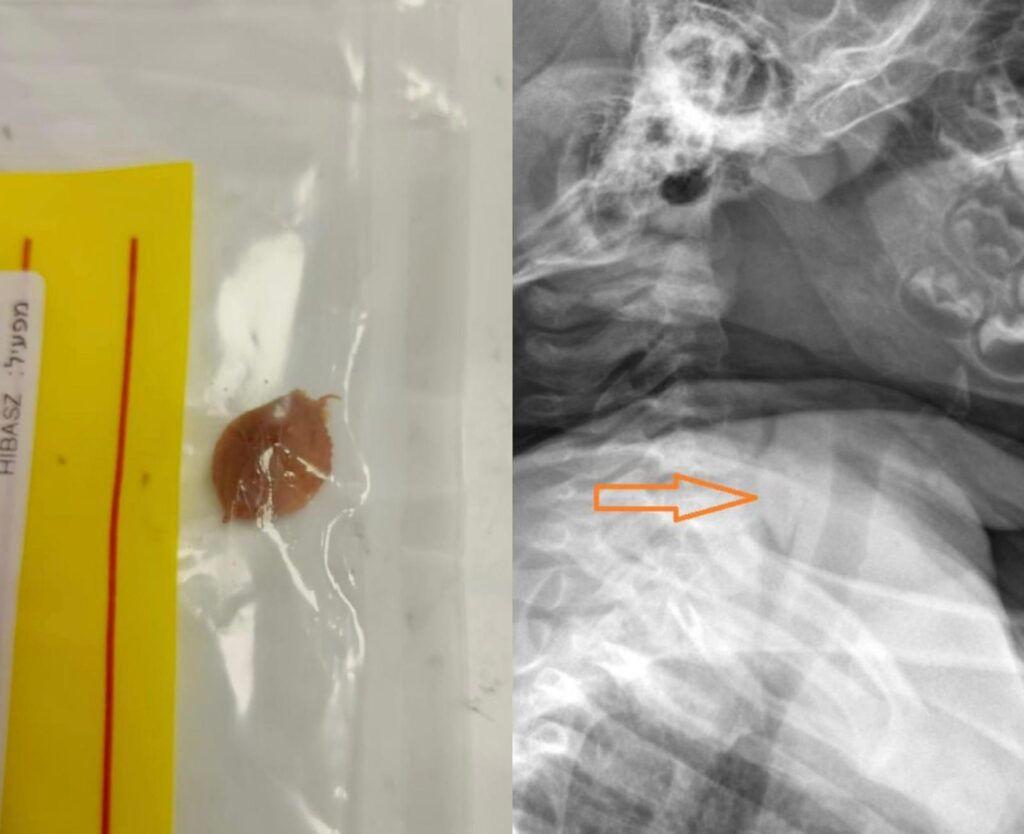

בחדר מיון ילדים, למרות שלא נצפה דבר בלוע, התעקשו לעשות בירור מקיף ובמסגרת בדיקות וצילום רנטגן שנערכו לתינוק, גילו הרופאים כי אכן הגלעין, נמצא בגופו של התינוק, ונתקע בחלק העליון של הוושט, סמוך לפתח קנה הנשימה.

"חשדנו שהגלעין נמצא בגופו של התינוק, והיינו חייבים לגלות היכן בדיוק" מסביר ד"ר מג׳ד עסאקלה שטיפל בתינוק "קיימנו בירור מקיף, ואכן במסגרת צילום צוואר צידי גילינו את הגלעין, במקום שסמוך לקנה הנשימה. היה פה נס גדול" הוא אומר "כאשר הגלעין נמצא בחלק העליון של הוושט, משם הדרך קצרה לקנה הנשימה כשהתינוק זז או אפילו משתעל. ואם הגלעין היה מגיע לקנה הנשימה – זה יכול היה לגרום לחסימת הנשימה ולחנק"

התינוק הובהל לחדר הניתוח, ותחת הרדמה כללית חילצו הרופאים את הגלעין בזהירות מגופו.